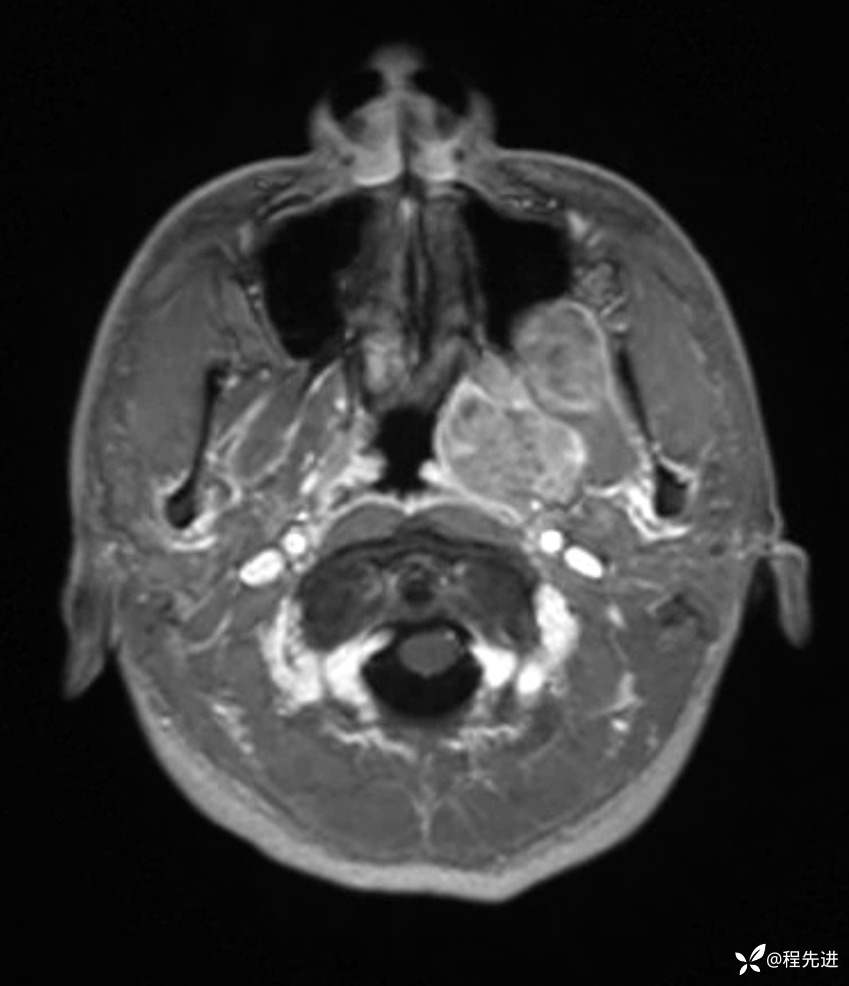

T1增强: